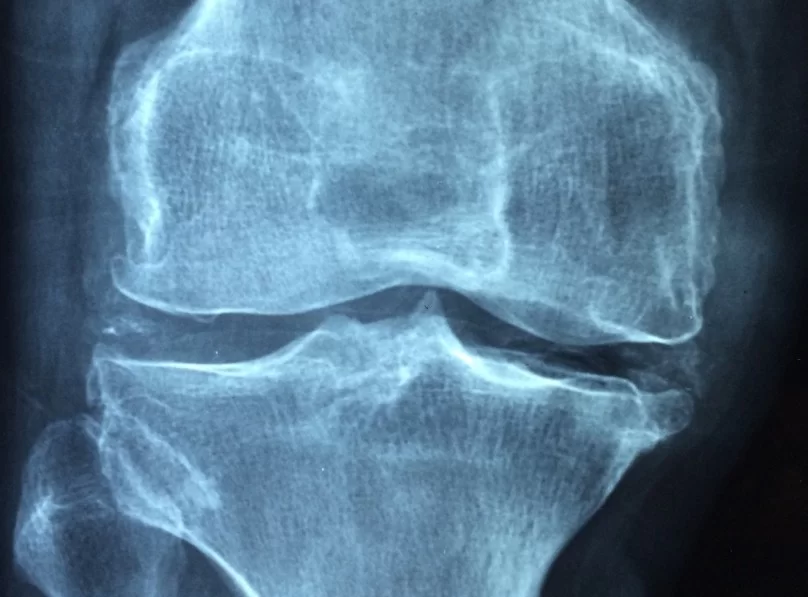

Шарнирный ортез помог уменьшить боль при остеоартрите коленного сустава

Мелани Холден из Килского университета вместе с коллегами провела клинические исследования и обнаружила, что использование шарнирного ортеза вместе с обычными методами лечения может быть эффективным и безопасным способом помощи при остеоартрите коленного сустава, особенно для снижения боли.

В рандомизированных мультицентровых слепых испытаниях приняли участие 466 пациентов (средний возраст — 64 года, 46% — женщины) с диагнозом остеоартрит коленного сустава. Все участники получили консультацию специалиста по лечебной физкультуре, печатные методические материалы и обучение гимнастике. Половине пациентов дополнительно подобрали подходящий шарнирный ортез — разгружающий бедренно-надколенниковое или бедренно-большеберцовое соединение либо неспецифический стабилизирующий бандаж — и провели мотивационную беседу о его ношении.

Через шесть месяцев результаты по шкале KOOS-5 оказались лучше у тех, кто носил ортез: скорректированная средняя разница составила 3,39 балла, средний размер эффекта — 0,24. Наибольший эффект отмечался в снижении боли — скорректированная средняя разница достигла 6,13 балла, средний размер эффекта — 0,39. К 12 месяцам различия между группами уменьшились. Серьезных или неожиданных побочных реакций на ношение бандажа не зафиксировано.